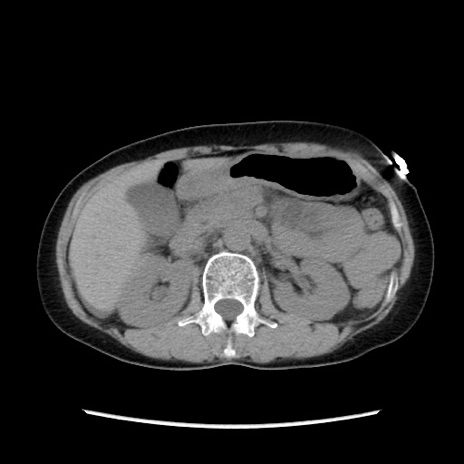

冠状断像

矢状断像